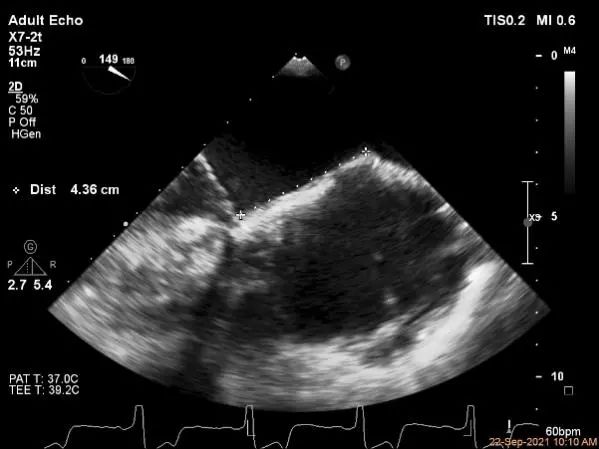

术前超声评估

P2区脱垂,宽14.8mm,Gap:3.3mm

穿刺高度:4.3cm